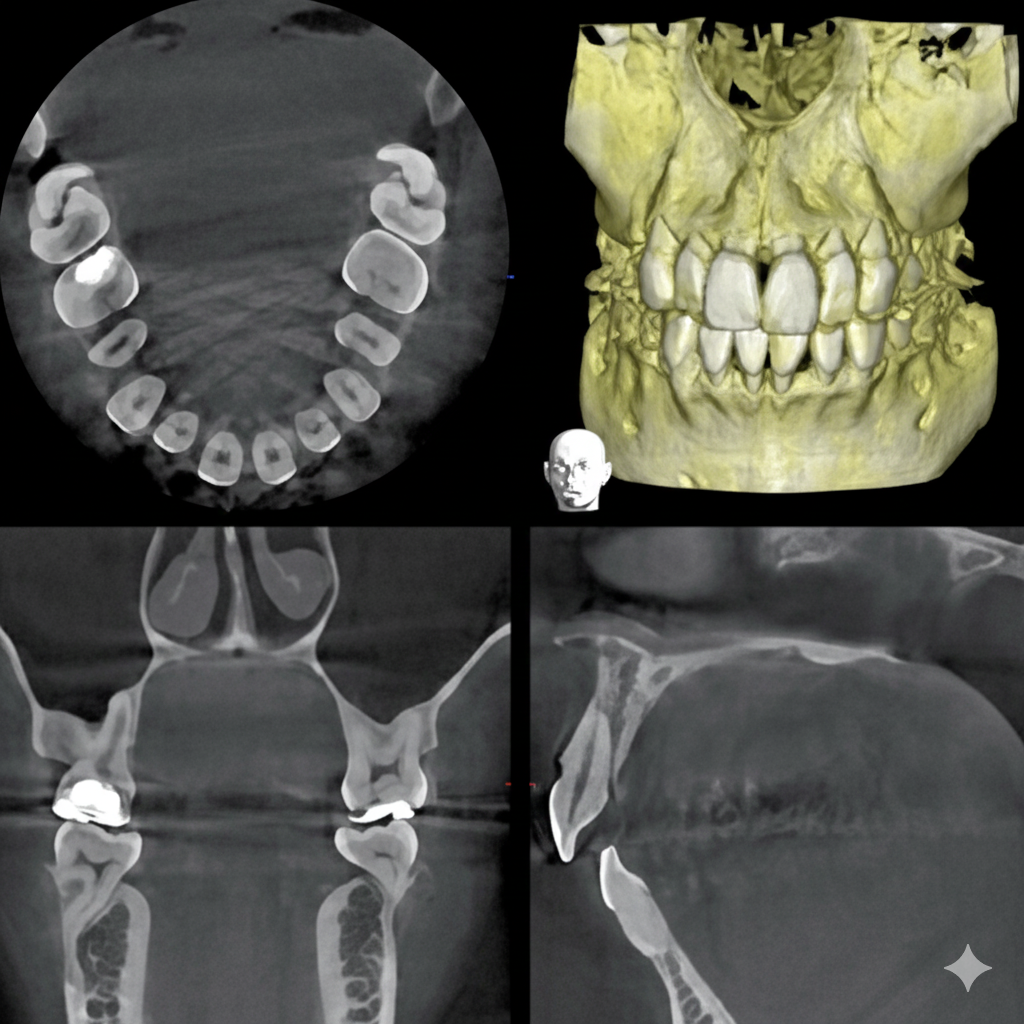

従来のレントゲン画像は平面像(二次元)でしたが、歯科用CT画像は立体画像(三次元)でみることが出来ます。

ですから、インプラントや歯周病などの診断に有効で、従来の平面画像では難しいとされた骨の幅の確認などが行えます。CT撮影で様々な角度から診断することで、正確な診査・診断に役立ち、より安全で確かな治療を行うことが可能となります。

CT画像からは、骨の形や欠損状態がわかるだけでなく、神経の位置や向きなどもしっかり把握できますので、特に、以下のような治療で役立っています。

インプラント治療では、CTの画像から埋入する部位の骨の状態(質や厚み、高さ、形態など)を正確に読み取り、そこから治療計画を立てることが出来ます。歯科用CTでの撮影画像をもとに、的確な治療計画を立てることは、安心な治療への第一歩です。また三次元の立体画像から、神経などを避けた安全な位置、方向、深さを決定し埋入する事が可能となり、より安心・安全な治療を提供する事が出来ます。

歯周病は、細菌感染による骨の破壊が起きる病気であるため、骨の破壊の程度などをよりリアルに見て判断することができます。また、骨の状態からおおよその 歯の寿命を積算することも可能です。従って、非常に予知性の高い治療が行えます。 歯科用CTを使った検診を行うことで、歯を支えている骨の状態などを直接的に見ることが出来ます。

歯の神経や根っこに潜む細菌をきれいに取り除く、根管治療。CT画像では、根の本数や神経の入っている管の方向、そして位置を正確に把握することができます。また、細かい根の破折も発見できるので、早期治療が可能になります。

歯科用CTを親知らずの抜歯に利用することで、神経までの正確な距離や、周囲の炎症の程度、病巣の有無や大きさ、位置なども判断・考慮して、治療を行うことができます。また埋伏歯などの位置なども精密に判断できるので、余分な切開や骨の切削などを避けることができます。